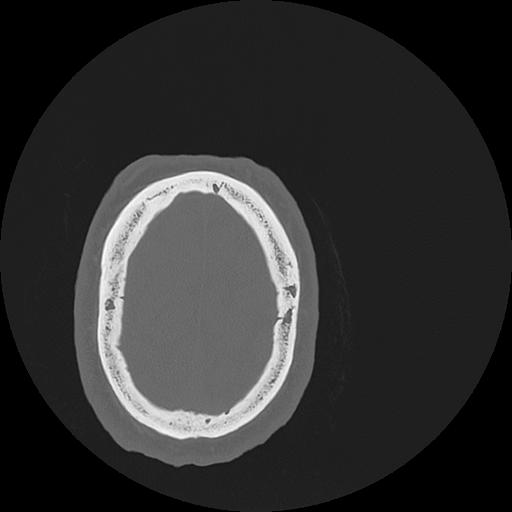

7 HUESO,,Vol,0.5,HUESO,,